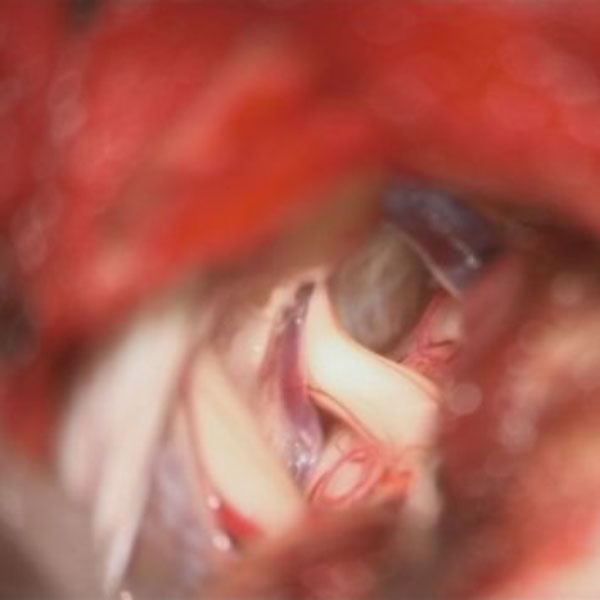

手術中

処置前

処置後